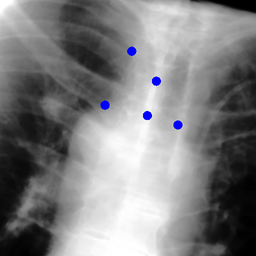

The dataset we use in the experiments is a cone-beam CT (CBCT) dataset captured for radiation therapy. The dataset contains 340 raw CBCT scans with each has 780 X-ray images. Each X-ray image comes with a geometry file that provides the registration ground truth as well as the information to reconstruct the CBCT volume. Each CBCT volume is reconstructed from the 780 X-ray images, and in total, we have 340 CBCT volumes (one for each CBCT scan). We use 300 scans for training and validation, and 40 scans for testing. The size of the CBCT volumes is 448×448×768448448768448\times 448\times 768 with 0.5 mm voxel spacing, and the size of the X-ray images is 512×512512512512\times 512 with 0.388 mm pixel spacing. During the experiments, the CBCT volumes are treated as the 3D pre-intervention data, and the corresponding X-ray images are treated as the 2D intra-intervention data. Sample X-ray images from our dataset are shown in Figure. Note that unlike many existing approaches [15, 17, 25] that evaluate their methods on small datasets (typically about 10 scans) which are captured under relatively ideal scenarios, we use a significantly larger dataset with complex clinical settings, e.g., diverse field-of-views, surgical instruments/implants, various image contrast and quality, etc.

Refer to caption

Figure 6: Sample raw X-ray images of our dataset.